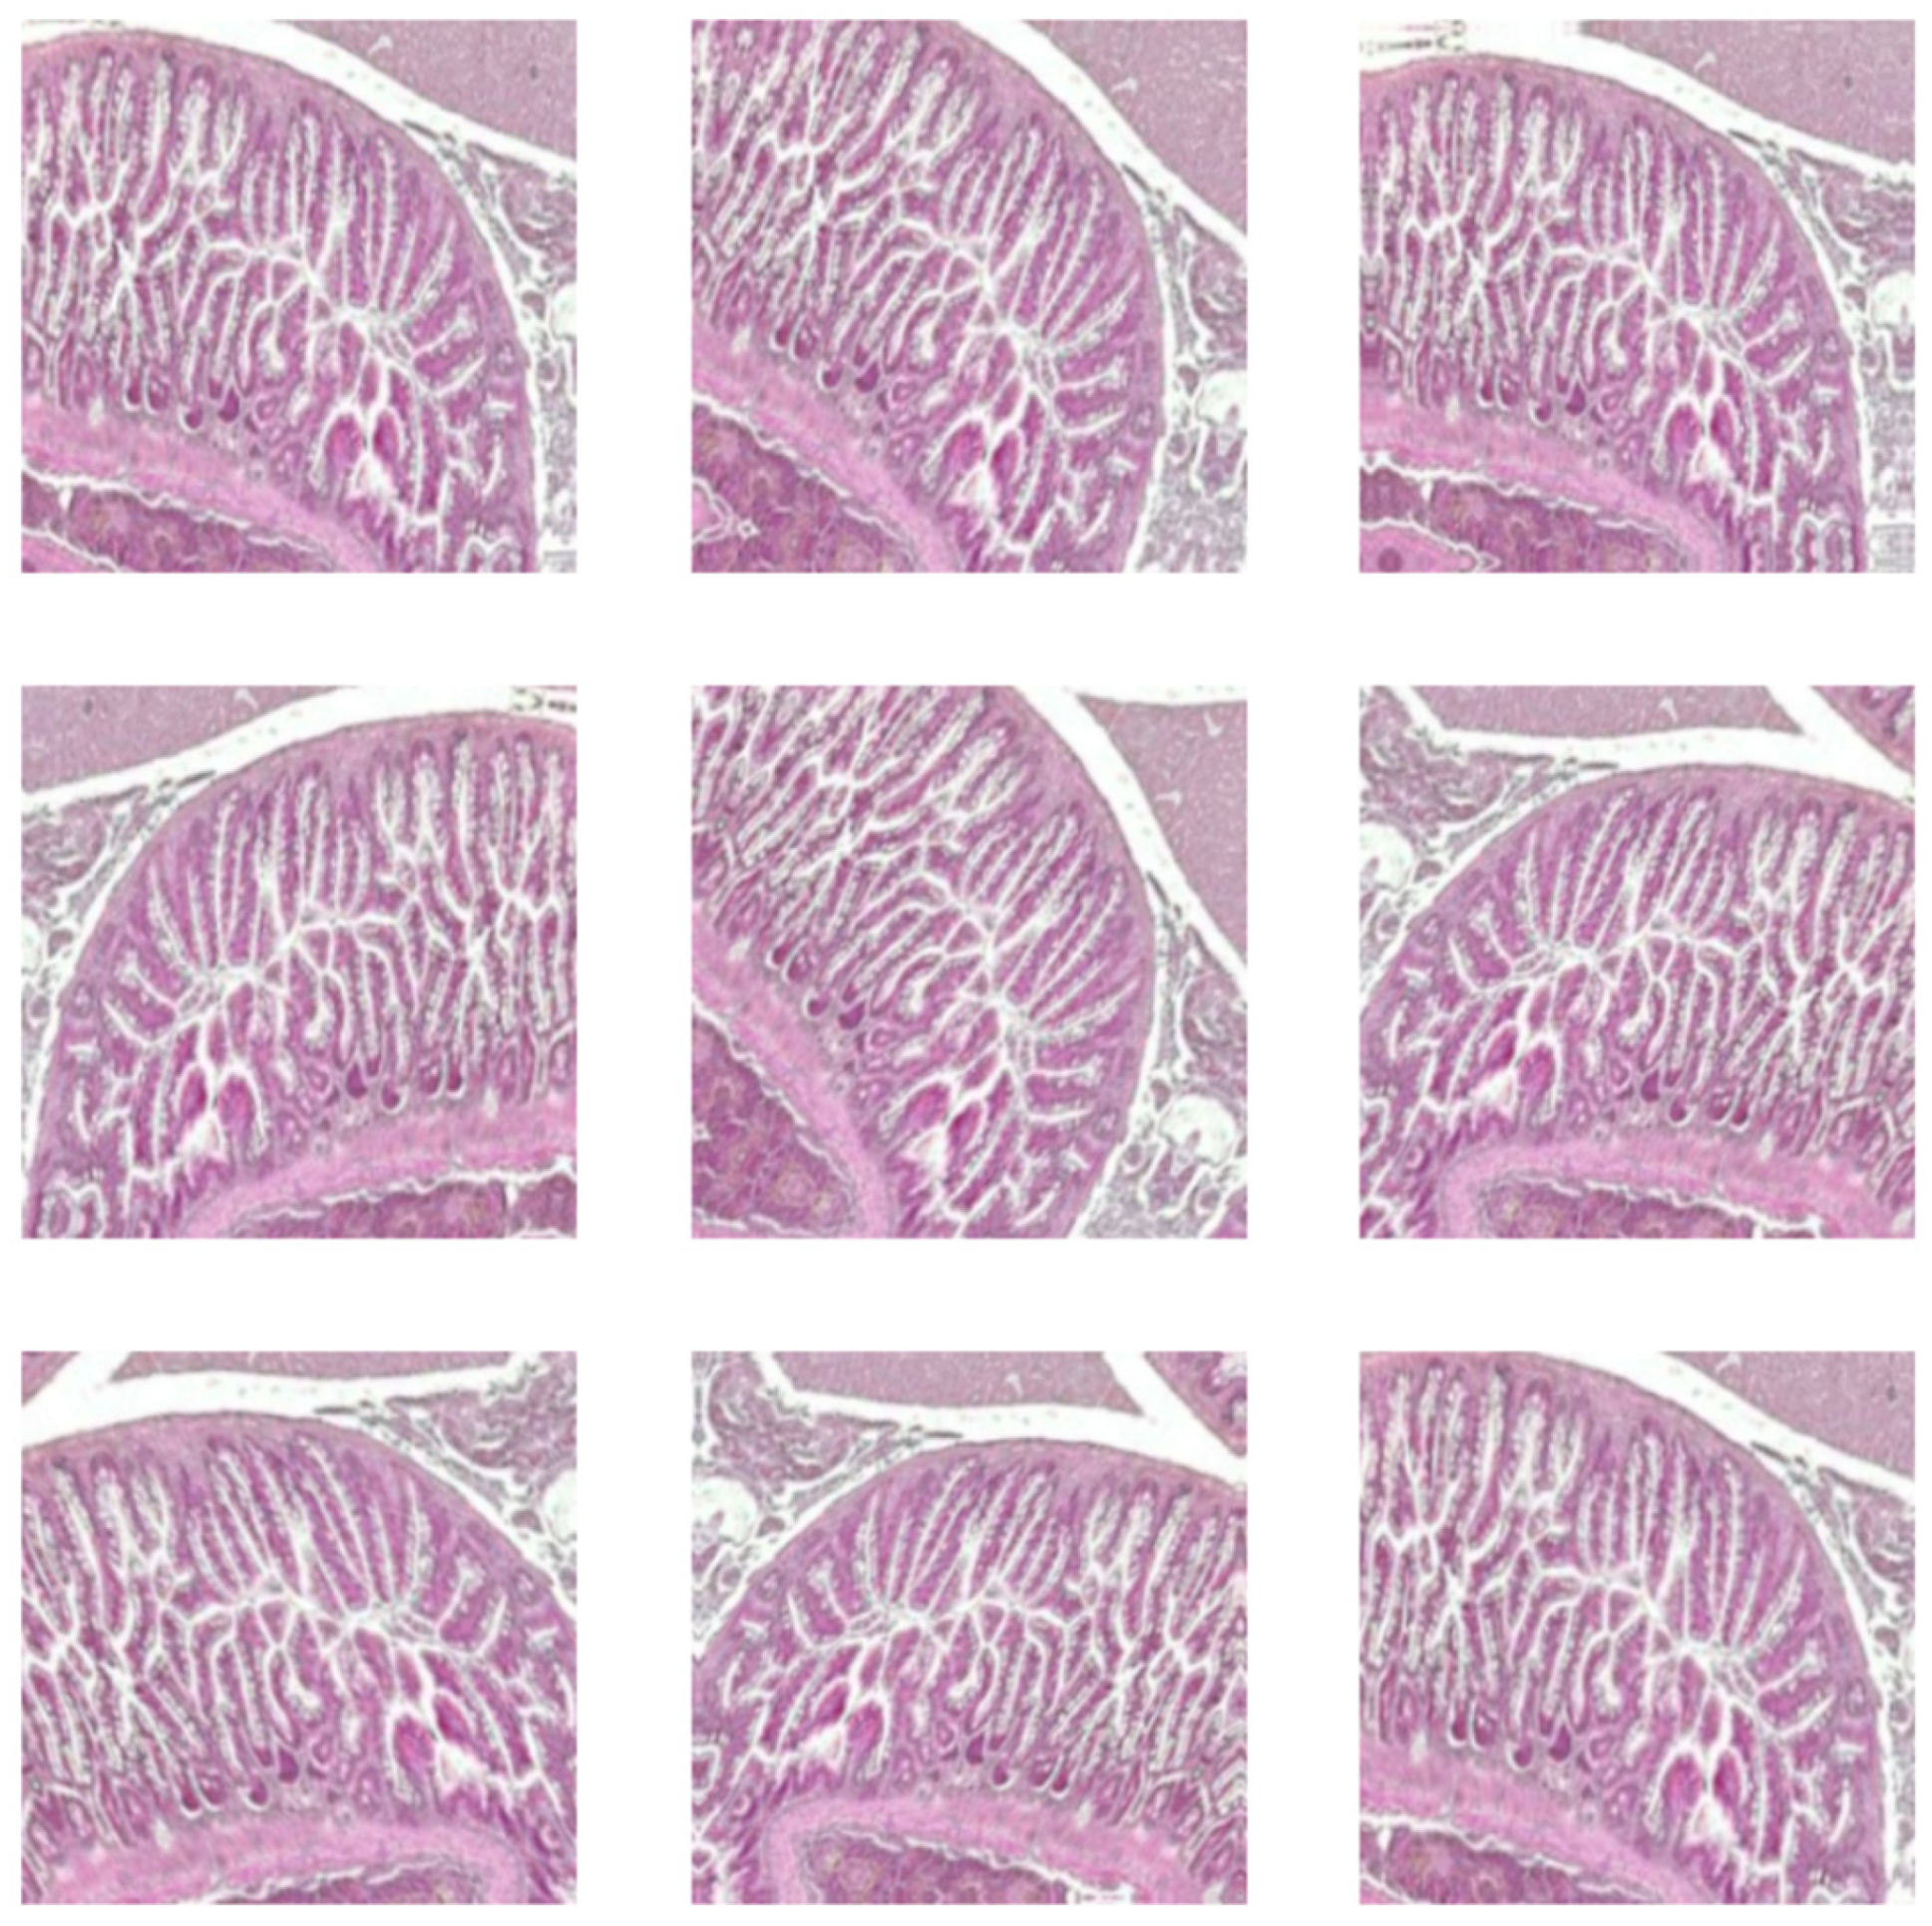

The original images were in RGB channels, and the pre-processed image was with CLAHE in grayscale. The size of images was established at 299 × 299 for Xception, 72 × 72 for ViT, and 250 × 250 for custom-built and autoencoder CNN. Figure 2 depicts samples from control, oxidative stress, oxidative stress and theobromine, and oxidative stress and caffeine histological images.

Figure 2. Samples form proposed dataset: zebrafish intestine. (a) control; (b) OS; (c) OS and TB; (d) OS and CAF. HE staining, 10×; scale bar, 100 μm.